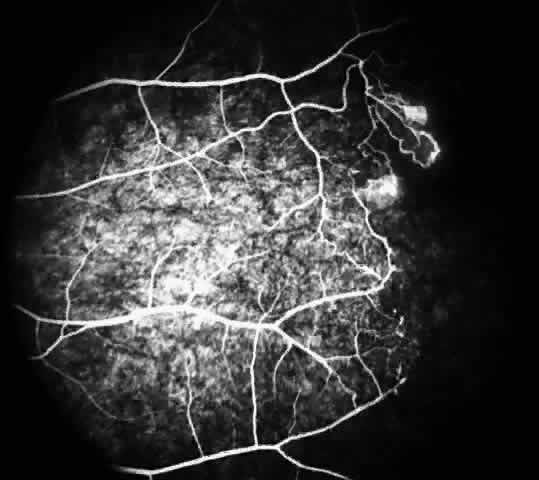

Other macular and perimacular changes include microaneurysm-like dots, dark and enlarged segments of arterioles, hairpin-shaped venular loops, pathologic avascular zones, and widening and irregularities of the foveal avascular zone (Figs. 11 and 12). In the Jamaican cohort study evaluating children with homozygous sickle cell anemia and SC disease between the ages of 5.0 and 7.5 years of age, no pathologic avascular zones could be identified despite a high incidence of peripheral vascular closure.31 In evaluating patients with homozygous sickle cell anemia, no relationship between ISC counts and macular abnormalities or visual acuity could be found.101 Using fluorescein angiography, investigators have found the foveal avascular zone to be significantly larger in eyes with clinical evidence of sickle cell maculopathy as compared with normal eyes and eyes without clinical evidence of sickle cell maculopathy.102–104

Fig. 11. A. A 40-year-old woman with homozygous sickle cell anemia. A fluorescein angiogram demonstrates multiple microaneurysm-like dots with fluorescein leakage, hairpin loop (arrowhead), pathologic avascular zones (arrows), and a widened, irregular foveal avascular zone (FAZ). B. Fluorescein angiogram of a 30-year-old woman with homozygous sickle cell anemia demonstrates multiple microaneurysm-like dots and a widened, irregular FAZ.

Fig. 12. A. Fluorescein angiogram of the left eye of a 40-year-old man with homozygous sickle cell anemia, demonstrating an irregular foveal avascular zone (FAZ), hairpin loops, and loss of the temporal capillary network. B. Fluorescein angiogram of the right macula of a 38-year-old woman with homozygous sickle cell anemia, showing an abnormal FAZ, hairpin loop (arrowhead), and pathologic avascular zones (arrows).